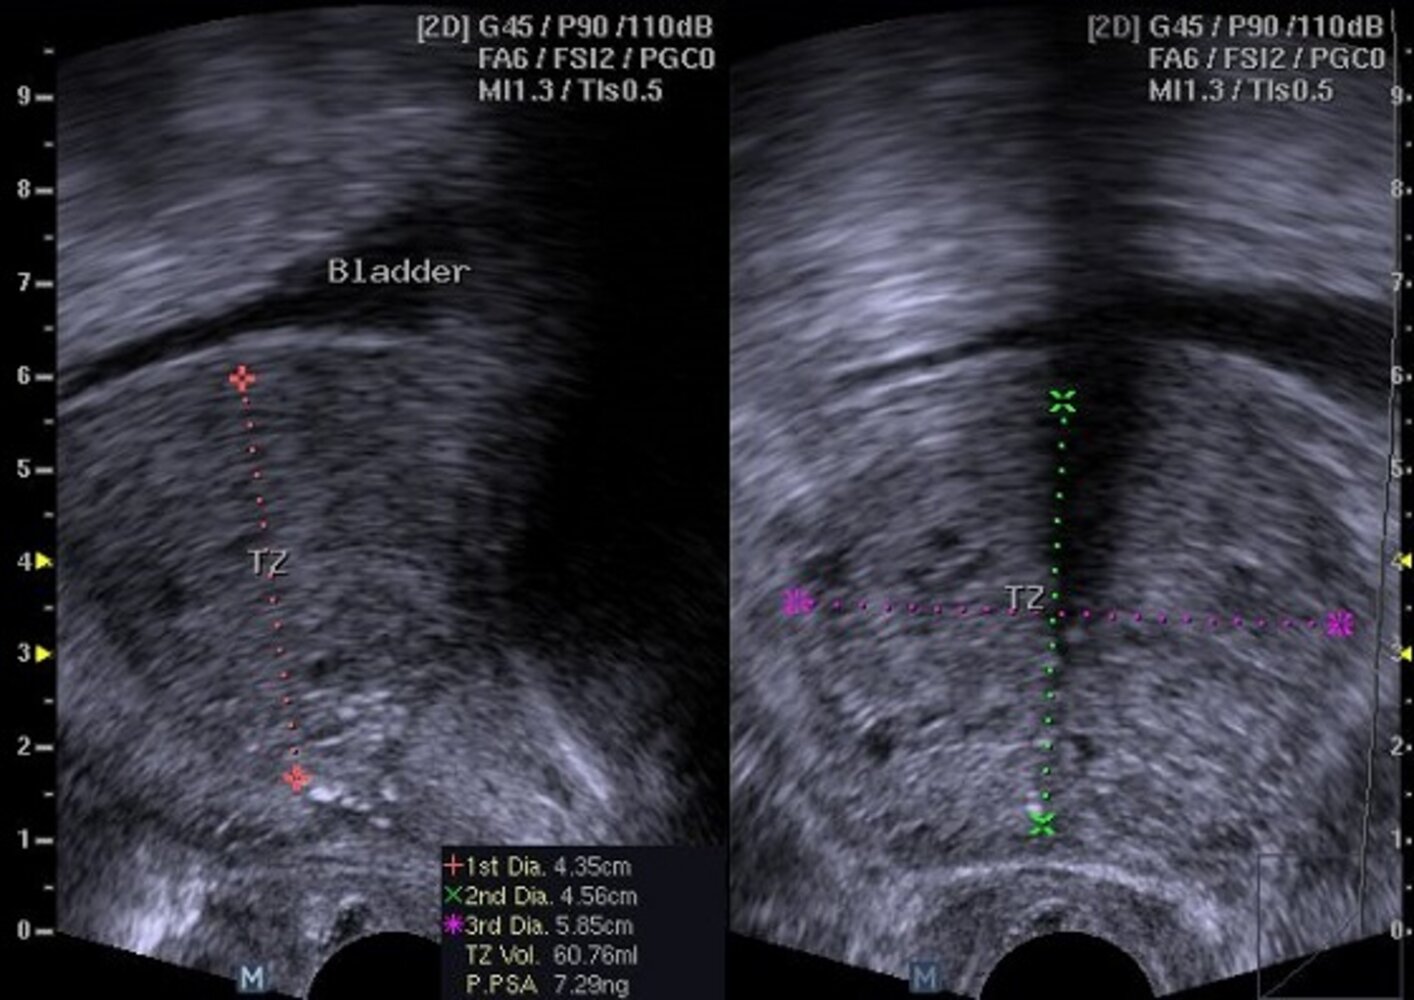

Imaging [18][20]

Imaging in patients with LUTS attributable to BPH is indicated to assess prostate size and morphology, if the results may affect treatment selection. Imaging may also be considered to rule out differential diagnoses or to assess for complications.

Ultrasound

• Indications [12]

• Ultrasound pelvis (bladder and prostate): Consider prior to initiating treatment to assess the size of the prostate and guide the choice of therapy.

• Ultrasound of the upper urinary tract: Consider in patients with significant PVR volume, hematuria, or suspected urolithiasis.

• Supportive findings of BPH

• Increased total prostate volume

• Elevated PVR volume (see β€œUrodynamic studies”) [21]

• Evidence of BOO (e.g., bladder wall thickening, hydronephrosis)

Transrectal ultrasound (TRUS) [20][22]

TRUS is not required for the initial evaluation of LUTS attributable to BPH. [18]

• Indications

• Suspected prostate cancer to guide biopsy

• To guide pharmacotherapy [12]

• Prior to surgical intervention

• Supportive findings of BPH: heteroechoic enlargement of the periurethral (transition) zones of the prostate